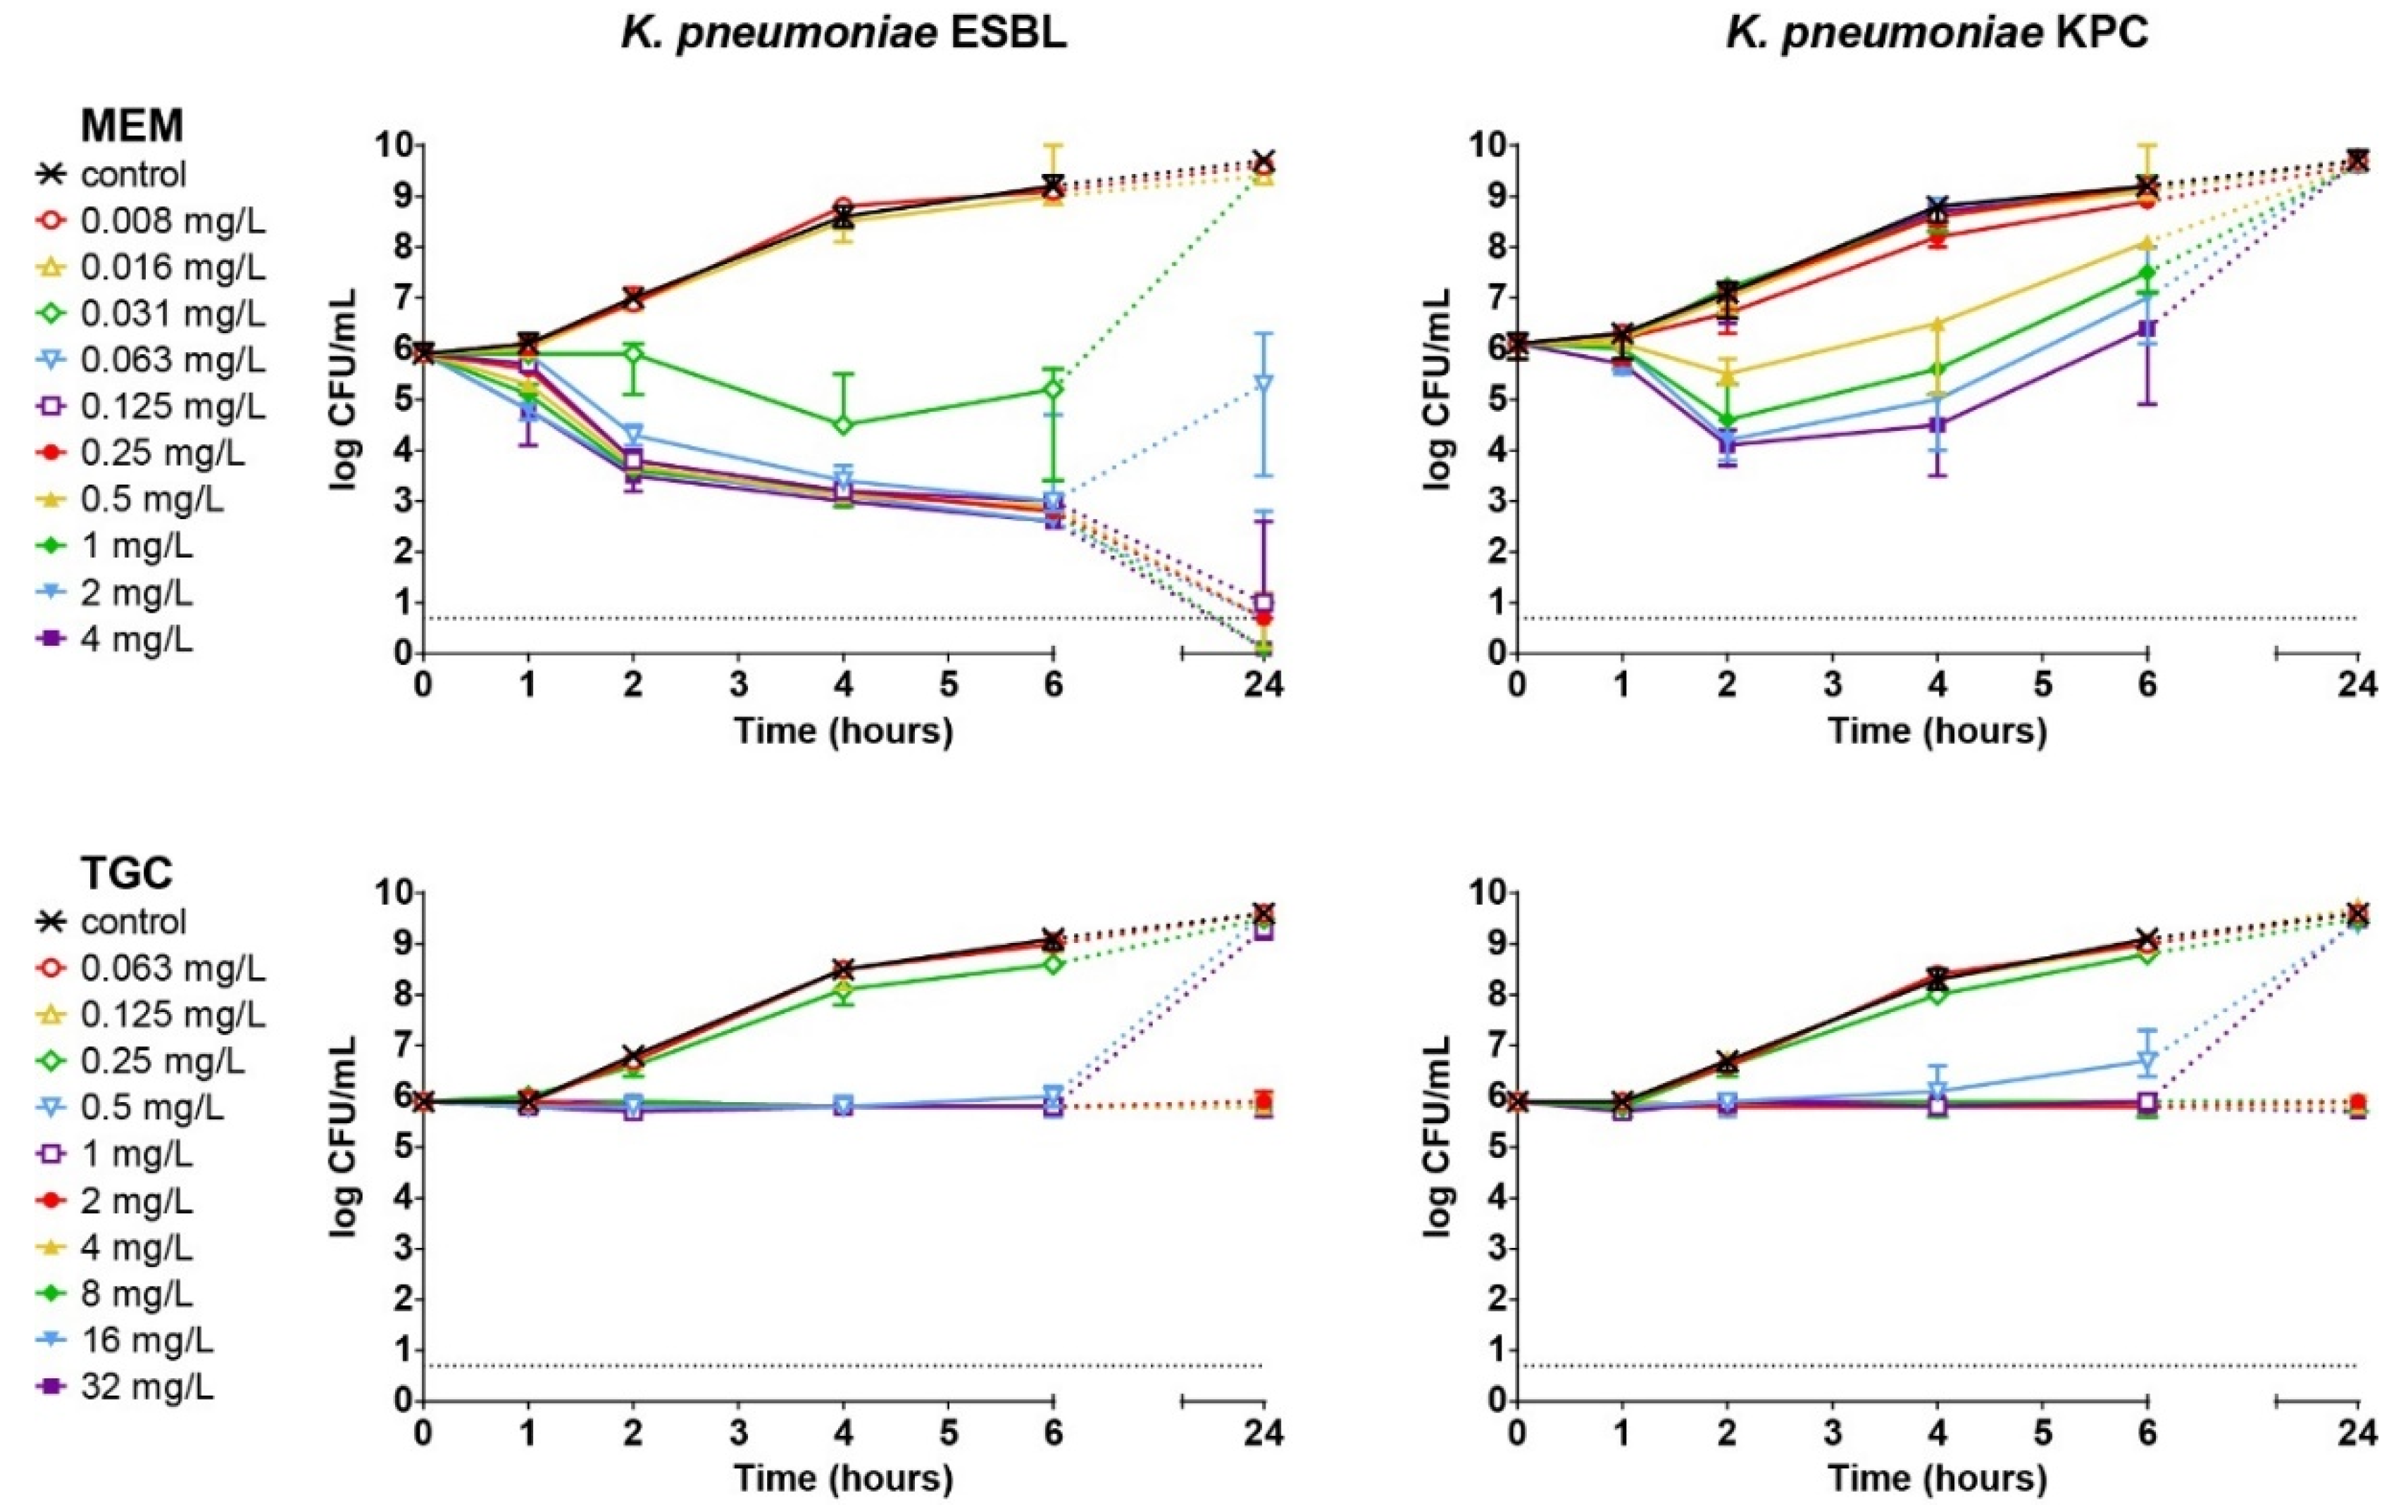

3.3. Concentration- and Time-Dependent Bactericidal Activity of Antibiotics In Vitro